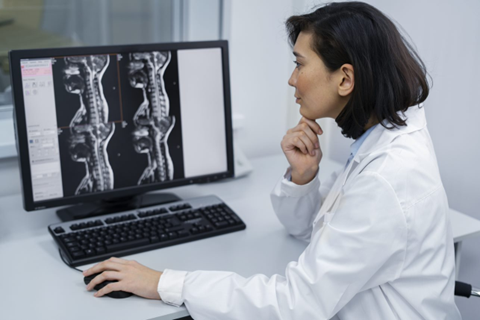

How MRI of the Lumbar Spine Helps Diagnose Back Pain and Other Spinal Issues

What is an MRI Lumbar Spine? An MRI Lumbar Spine is a special scan that uses strong magnets and radio waves. It creates clear pictures